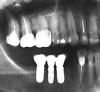

Несмеяна Опубликовано 3 февраля, 2010 Поделиться Опубликовано 3 февраля, 2010 Здравствуйте, уважаемые доктора. Буду признательна, если поможете мне в решении некоторых вопросов.По первому снимку:1) Верхняя пятерка и семерка слева слегка подвижны, имеют клиновидный дефект. Врач рекоменовал 5 - умертвить и сделать мост (5 и 7 под опору). Мотивируя тем, что мост укрепит 5 и 7 зуб - и уменьшит нагрузку. Ну и 3 дня назад удалил нерв из 5 зуба и запломбировал гуттаперчей.Позавчера порывшись в интернете обнаружила, что не следует делать мосты на подвижных зубах и мост только усилит нагрузку на них. 5 - жалко, но ничего не попишешь,дело сделано.Имплант пока поставить не могу, т.к. он подразумевает синус -лифтинг, а это все вместе дорого, а у меня по плану и так расходы на зубы грядут великие, в т.ч. имплантация зуба в нижнем ряду.Можно ли эти 2 зуба посадить под коронку и нужно ли делать вкладку? Стоит ли тянуть с имплантацией ( не рассосется ли кость совсем?) или дождаться пока пошатывающиеся зубы наконец выпадут, а потом сделать синус-лифтинг и пару имплантов?Посоветуйте, что мне с ними делать? 2) Можно ли поставить коронку на нижнюю шестерку в том состоянии как есть, или надо перелечивать и вкладку ставить? По второму снимку: 1) Можно ли на верхней шестерке (зуб резорциненный, не беспокоит более 15 лет) поменять коронку без прохождения каналов?2) Нужно ли на 2 верхний справа одевать коронку или можно закрыть его виниром?Он мертвый. Если коронку, то какую, чтобы не почернела у десны? И еще вопрос, не знаю только к трапевтам или к ортопедам, Эмаль передних зубов сильно стирается изнутри, зубы нарощены, но чувствительность на холод сильная. Что лучше в данном случае - коронки или виниры, и можно ли вообще винирами закрыть внутреннюю сторону зуба? Жалко их умертвлять подкоронки... Спасибо. Извините, что так много вопросов. Ссылка на комментарий

Андрей Опубликовано 5 февраля, 2010 Поделиться Опубликовано 5 февраля, 2010 Семерку слева надо не под мост брать, а удалять, как обе восьмерки. Не укладываетесь в синуслифтинг - сделайте на время съемную конструкцию. Потом ее замените на имплантаты.Все зубы с лечеными каналами надо переделать и покрыть коронками. Ссылка на комментарий

Sir Edward'S Опубликовано 6 февраля, 2010 Поделиться Опубликовано 6 февраля, 2010 Здравствуйте, уважаемые доктора. Буду признательна, если поможете мне в решении некоторых вопросов.По первому снимку:1) Верхняя пятерка и семерка слева слегка подвижны, имеют клиновидный дефект. Врач рекоменовал 5 - умертвить и сделать мост (5 и 7 под опору). Мотивируя тем, что мост укрепит 5 и 7 зуб - и уменьшит нагрузку. Ну и 3 дня назад удалил нерв из 5 зуба и запломбировал гуттаперчей.Позавчера порывшись в интернете обнаружила, что не следует делать мосты на подвижных зубах и мост только усилит нагрузку на них. 5 - жалко, но ничего не попишешь,дело сделано.Имплант пока поставить не могу, т.к. он подразумевает синус -лифтинг, а это все вместе дорого, а у меня по плану и так расходы на зубы грядут великие, в т.ч. имплантация зуба в нижнем ряду.Можно ли эти 2 зуба посадить под коронку и нужно ли делать вкладку? Стоит ли тянуть с имплантацией ( не рассосется ли кость совсем?) или дождаться пока пошатывающиеся зубы наконец выпадут, а потом сделать синус-лифтинг и пару имплантов?Посоветуйте, что мне с ними делать? 2) Можно ли поставить коронку на нижнюю шестерку в том состоянии как есть, или надо перелечивать и вкладку ставить? По второму снимку: 1) Можно ли на верхней шестерке (зуб резорциненный, не беспокоит более 15 лет) поменять коронку без прохождения каналов?2) Нужно ли на 2 верхний справа одевать коронку или можно закрыть его виниром?Он мертвый. Если коронку, то какую, чтобы не почернела у десны? И еще вопрос, не знаю только к трапевтам или к ортопедам, Эмаль передних зубов сильно стирается изнутри, зубы нарощены, но чувствительность на холод сильная. Что лучше в данном случае - коронки или виниры, и можно ли вообще винирами закрыть внутреннюю сторону зуба? Жалко их умертвлять подкоронки... 1) чем дольше вы откладываете с удалением и имплантацией тем меньше останется костной тканитам уже имеется воспалительный процессмостовидный протез не стоит делать .он еще больше нагрузит подвижные зубы.лучше удалить и сделать сьемный протез с целью сохранения ваших передних зубов.2) конечно можно сделать все,но лучше перелечить зуб(каналы не запломбированы)изготовить культевую вкладку и покрыть зуб коронкой.коронку любую на ваш выбор.с передними зубами нужно заниматься только после решения всех проблем с жевательными зубами.можно закрыть винирами и сохранить их живыми Ссылка на комментарий